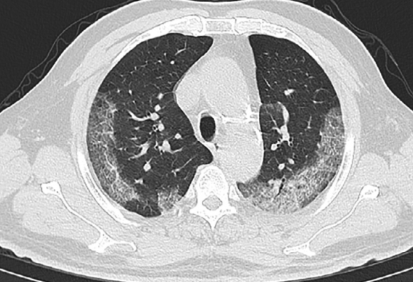

-의사 소견에 따라 입원이 필요한 원인미상 폐렴인 자

-입원이 필요하지 않는 원인미상 폐렴.

검사방법은 호흡기에서 검체를 채취한후 구인두(입)과 비인두(코)등에서 멸균한 플라스틱 면봉을 사용해 검체를 채취한다고 합니다. 3중 포장이되어 검사실로 이동을하고 임상병리사가 검사를 한다고 합니다. 대략적인 기간은 빠르면 6시간 늦으면 3일정도 걸린다고 합니다.